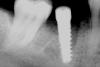

Два недели назад на месте удалённого зуба 6-го в низу с правой стороны поставили имплант.

Как я понимаю, он должен находиться по середине, между 5-м и 7-м, но у меня он сдвинут к 7-ке.

скорее всего прошло немного времени после удаления и врач установил имплант в позицию дистального корня 46-го зуба.

удаление 6-ки было четыре месяца назад, имплантация 27 октября. На фото - только что швы сняли.

прицельный сделан сегодня.

можно переставить имплантат ближе к центру. Интеграции еще нет. Можно попытаться использовать даже имеющийся имплант. Только теперь уже не с формирователем десны, а просто с заглушкой.

поговорила я с доктором, сказал что всё хорошо, что именно так он и планировал поставить имплант,

более того, он никогда ровно не ставит, что такая постановка - хорошо для гигиены, потому что с одной стороны коронка будет плотно прилегать к зубу, а с другой хорошо будет чиститься флосом.

сказал, что в случае "рюмки" (когда имплант стоит по середине) с двух сторон будут проблемы с гигиеной.

В итоге у меня будет стоять коронка-консоль. Знаю что консоль на зубе не желательна, именно из-за консоли я потеряла один зуб.